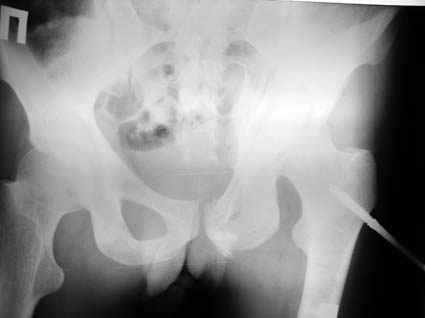

Уважаемые коллеги! Хотелось бы услышать совет по тактике лечения представлленого больного.Поступил после лечения в одном изотделений области. Травма 2,5 месяца назад. После выведенияиз шока был произведен остеосинтез перелома бедра, предплечья, до перевода к нам проводилосьвытяжение по оси шейки бедра за стержень, введенный в большой вертел. На сегодня деформацияригидна, клинически мобильности не определяется. Заранее признателен. P.S. Данный вид травм не включен в перечень "высокотехнологичных операций", направить длялечения по квотам Минздрава очень сложно.

Это обзорные и косые снимки

Привет, Леонид. Оскольчатый высокий двухколонный перелом в такие сроки трогать не надо, т.к. это про такие переломы сказано: "кто с ножом на Ж. пойдет тот в ней и останется...".